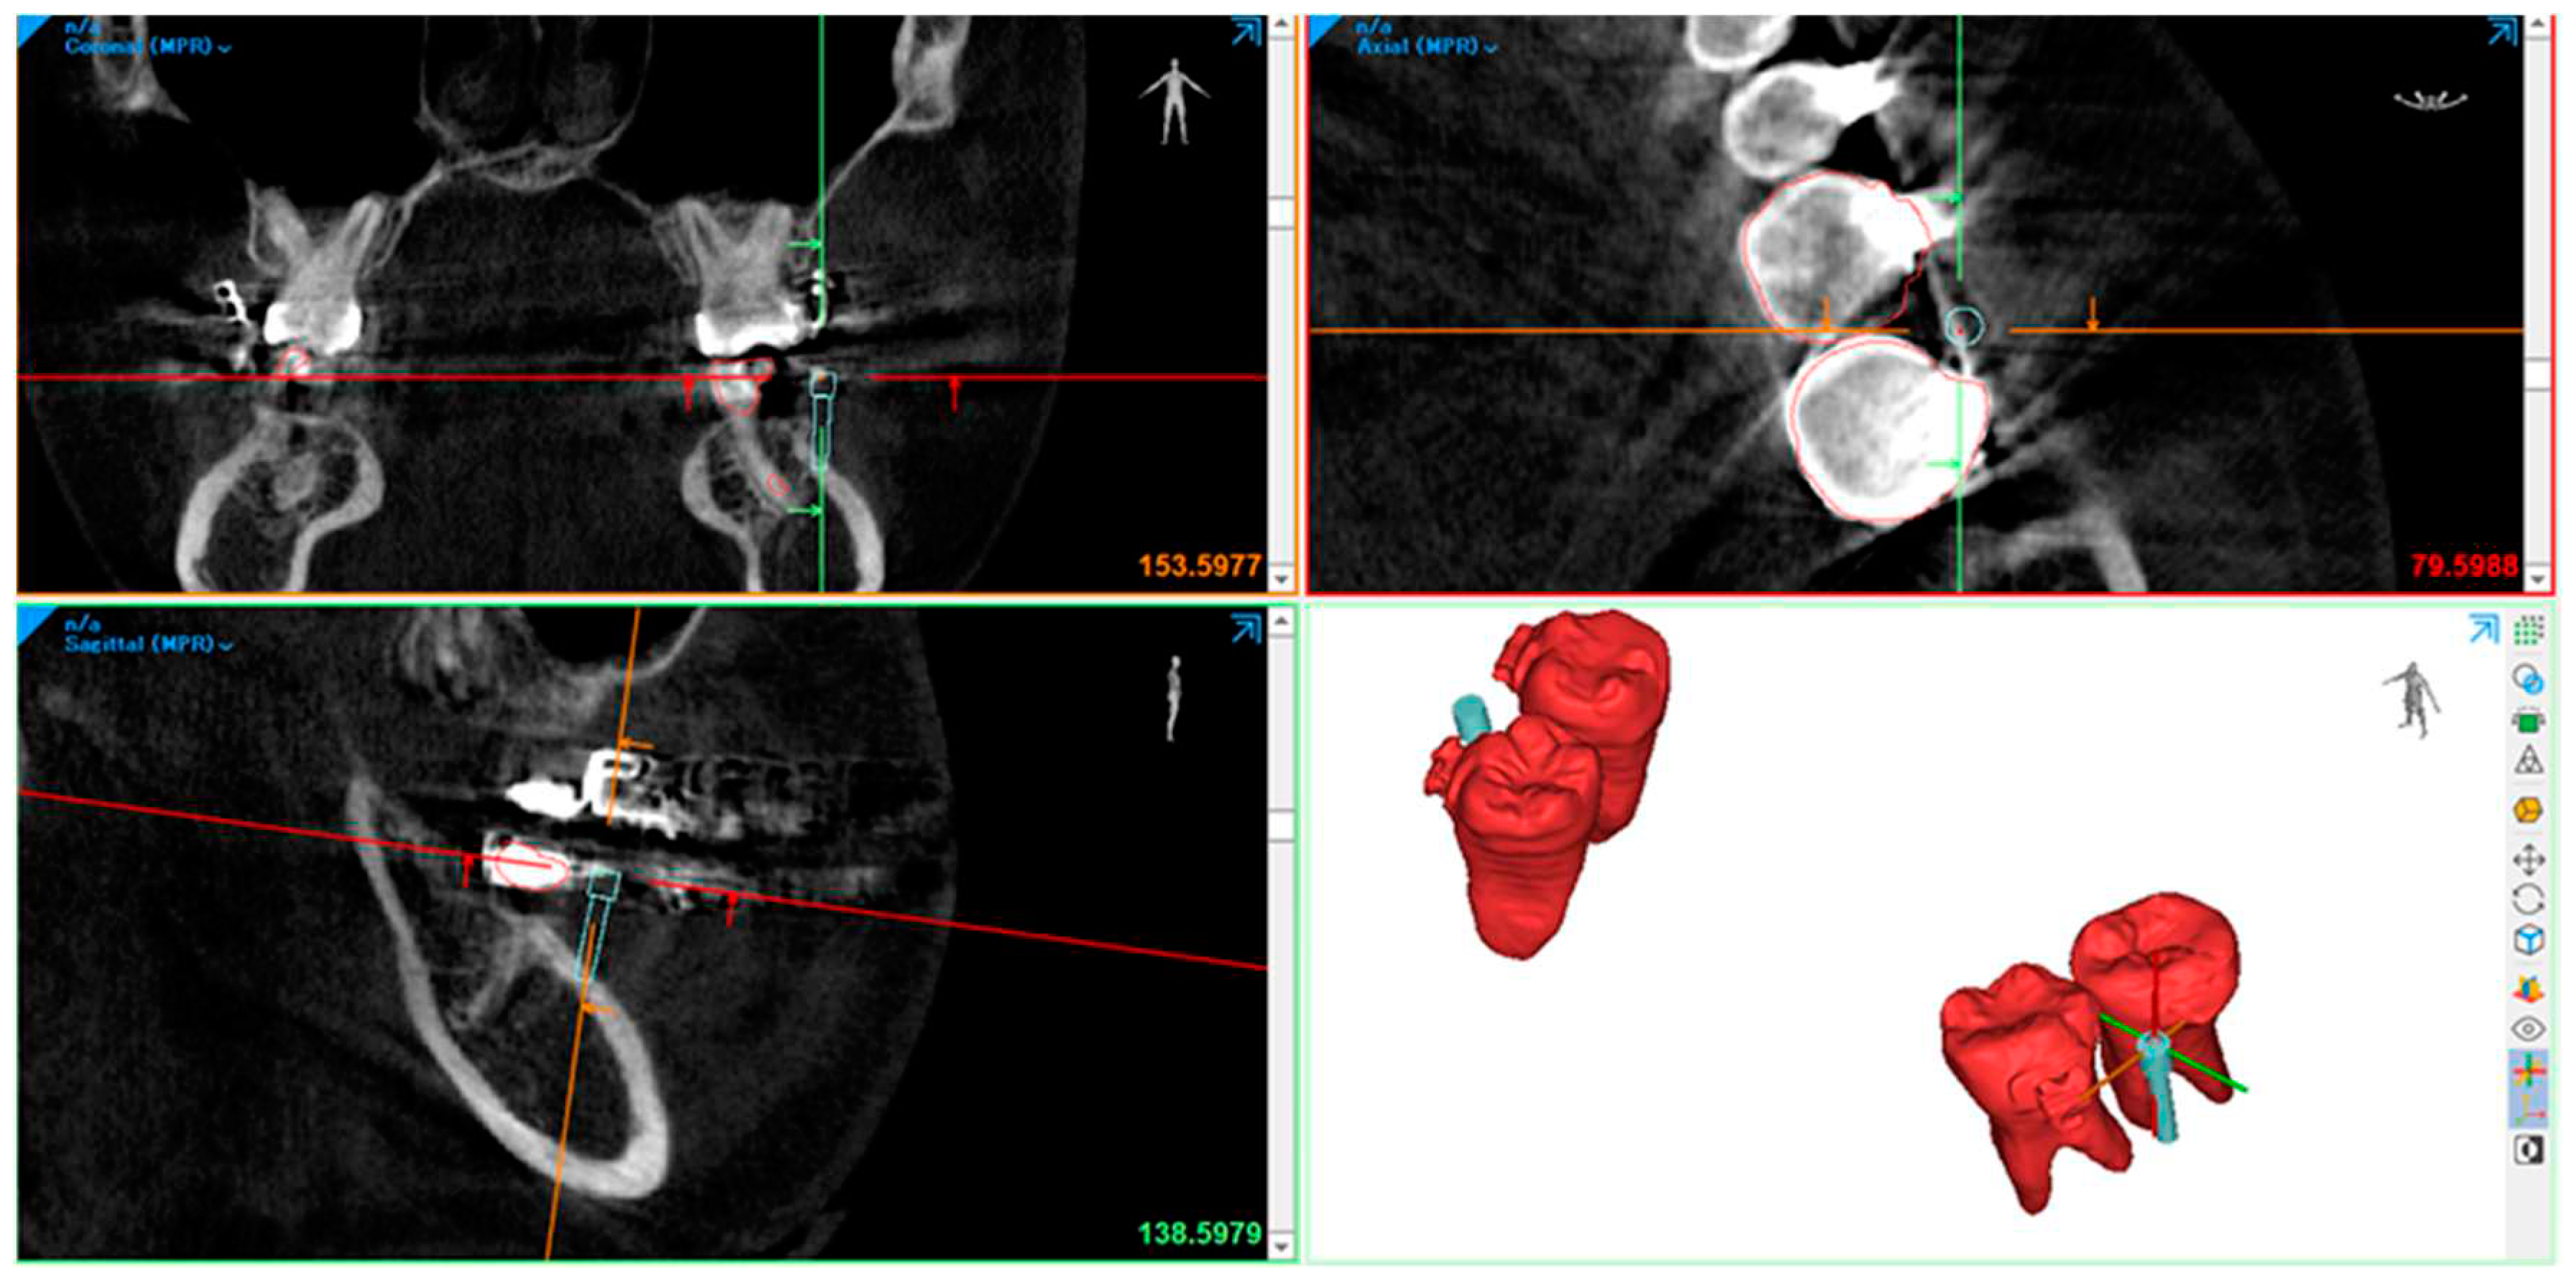

- We used an intra-oral scan for the SLT and a CBCT X-ray machine for the DICOM data to obtain a digital impression. afterward, we superimposed the STL and DICOM data using a commercialized application.

- The 3-Shape software completes the process of designing a surgical guide. By utilizing software, the diameter of the drilling bur and screw holder can be determined, ensuring no contact with the roots during the procedure. The 3-shape software simulates the screw placement within the bone's anatomic area. This simulation helps determine the tube design required for drilling and screw implantation.